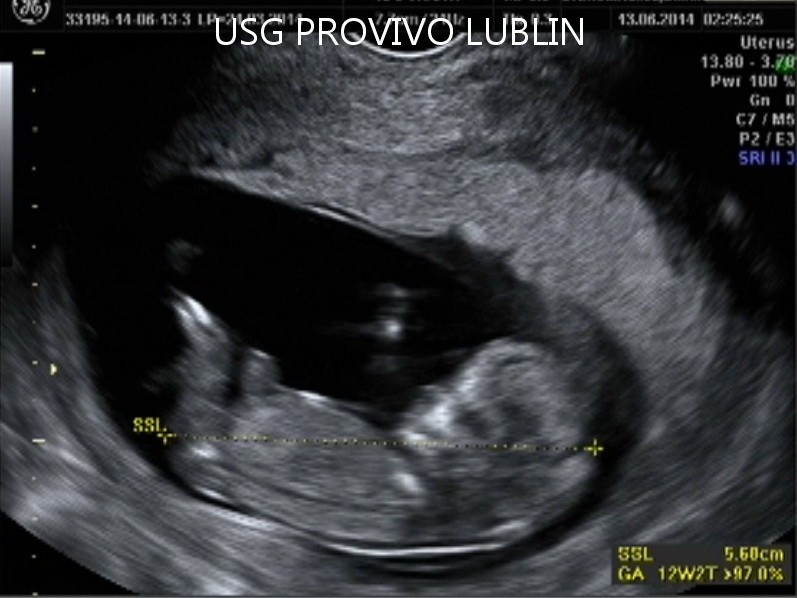

Podczas klasycznego badania USG 2D powstaje obraz dwuwymiarowy. Lekarz specjalista może z niego odczytać między innymi wielkość i kształt poszczególnych części ciała dziecka, a także ilość wód płodowych. Można w ten sposób określić także z dużym prawdopodobieństwem płeć dziecka. Aparaty nowej generacji pozwalają także na ocenę przepływu krwi przez naczynia krwionośne płodu i matki, dzięki czemu można otrzymać informacje dotyczące funkcji serca i łożyska.

W trakcie ciąży takie badanie może być wykonane między 11-14 tygodniem ciąży, a potem około 20 lub 30 tygodnia.